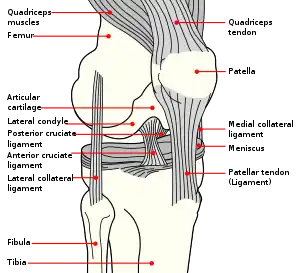

The knee joint is formed by three bones: the femur (thighbone), the tibia (shinbone), and the patella (kneecap). These bones are held together by ligaments, which are strong bands of tissue that keep the joint stable while an individual is walking, running, jumping, etc. There are two types of ligaments in the knee: the collateral ligaments and the cruciate ligaments.

The collateral ligaments include the medial collateral ligament (along the inside of the knee) and the lateral or fibular collateral ligament (along the outside of the knee). These two ligaments function to limit sideways movement of the knee.[6]

The cruciate ligaments form an "X" inside the knee joint with the anterior cruciate ligament running from the front of the tibia to the back of the femur, and the posterior cruciate ligament running from the back of the tibia to the front of the femur. The anterior cruciate ligament prevents the tibia from sliding out in front of the femur and provides rotational stability.[6]

There are also two C-shaped structures made of cartilage called the medial meniscus and lateral meniscus that sit on top of the tibia in the knee joint and serve as cushion for the bones.[1]

| Right knee, front, showing interior ligaments | Left knee, behind, showing interior ligaments |